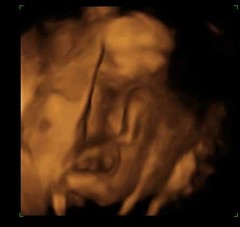

WE ARE TEAM BLUE AND I CRIED SO HARD!! OH thought it was hilarious and took photos... Git 😂 we went shopping after and bought some really cute boy stuff!!

Wasn't expecting much from the 3D peek but my god does nugget look like his dad! 😊😊 it's been a very good day ❤